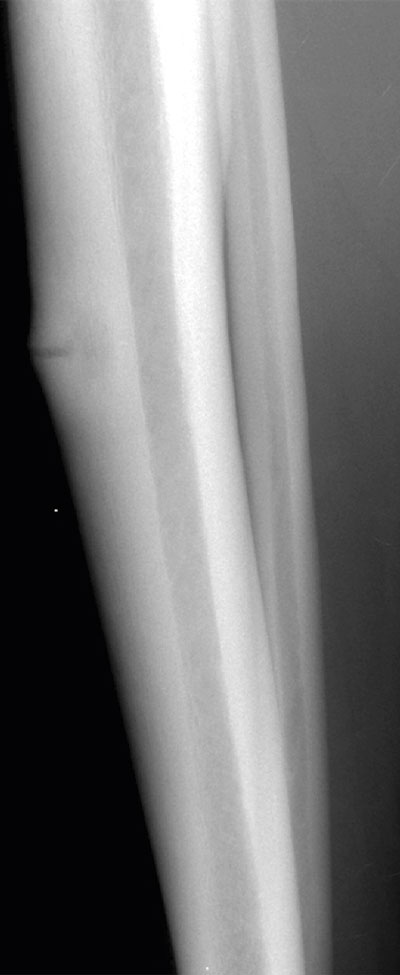

Belastningsutlösta smärtor och ömhet i benet omkring frakturen är typiskt vid stressfraktur [20]. Smärtorna minskar med vila. I de allra flesta fall kan slätröntgen ge diagnosen [21]. Efter några veckor bildas en kallusreaktion, som man kan se som en benpålagring både periostalt och endostealt. Ibland kan man se en frakturlinje som löper vinkelrätt mot benets längsaxel (Figur 5). Sprickan kan dock vara för tunn för att synas.

Figur 5. Stressfraktur med tvärgående frakturlinje och kallusreaktion i tibia (överst) och femte metatarsalbenet (ovan).